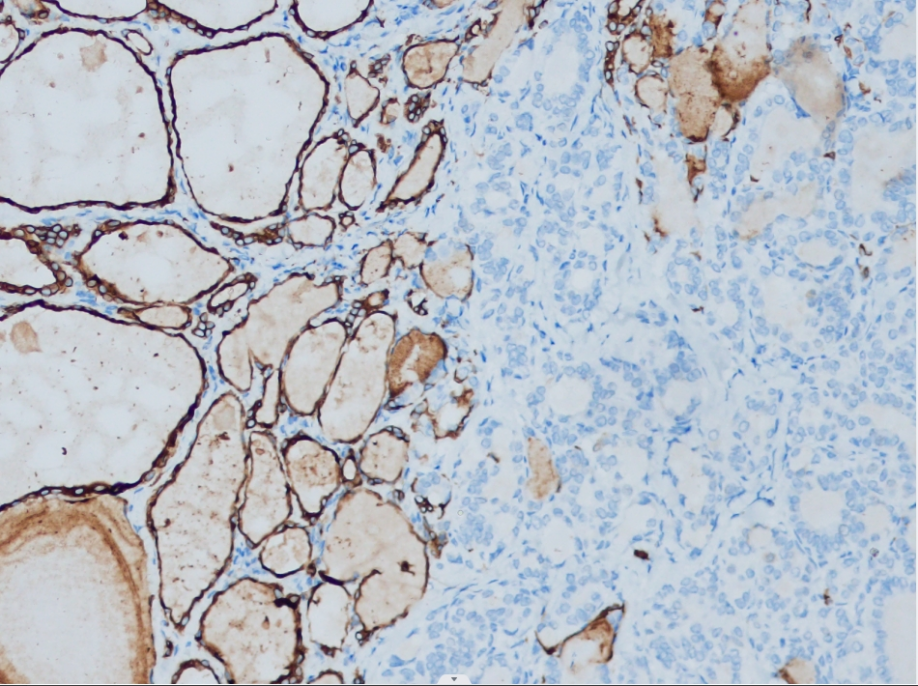

Positive control: Thyroid

Thyroid peroxidase (TPO) is located on the apical free surface of thyroid epithelial cells and directly participates in the oxidation of iodine, the iodination of tyrosine, and the coupling of iodinated tyrosine in thyroid cells. It is a key enzyme in the synthesis of thyroid hormones. It is highly expressed in normal, hyperplastic, and most benign thyroid tissues, but its expression is significantly reduced in malignant thyroid tumors. Therefore, this antibody can be applied to the study of benign and malignant thyroid tumors.

TPO antibody reagents can specifically bind to TPO molecular antigens. Immunohistochemistry kits containing TPO antibody reagents are suitable for the accurate diagnosis of benign and malignant thyroid tumors.